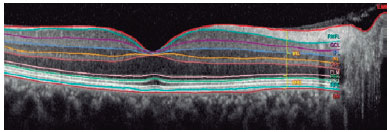

Retinal OCT imaging was performed using the Spectralis OCT system (Heidelberg Engineering GmbH, Heidelberg, Germany). Segmentation of the retinal layers from each SD-OCT scan was performed using the built-in Spectralis mapping software the Heidelberg Eye Explorer (version 6.0). Spectralis segmentation software was used to obtain the following thickness measurements: total retinal thickness (Retina), retinal nerve fiber layer (RNFL), ganglion cell layer (GCL), inner plexiform layer (IPL), inner nuclear layer (INL), outer plexiform layer (OPL), outer nuclear layer (ONL), and retinal pigment epithelium (RPE). The automatic segmentation tool of the posterior pole scan also provides the thickness of the inner retinal layer (IRL), measured from the internal limiting membrane to the external limiting membrane (ELM), and that of the outer retinal layer (ORL), measured from the ELM to the Bruch membrane (Figure 1). The Spectralis mapping software generates automated retinal thickness measurements based on analyses of the central, inner ring, and outer ring subfields as defined by the Early Treatment Diabetic Retinopathy Study (ETDRS)(12).

Figure 1. Segmented view of the retinal layers created using the Heidelberg Spectralis automatic segmentation analysis program.